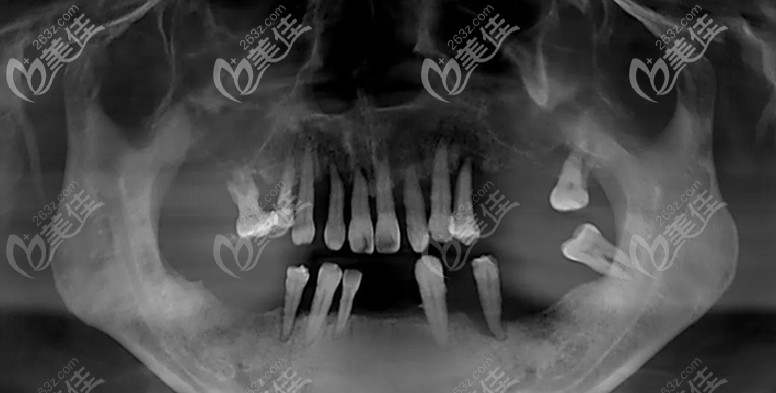

▲种植前的口腔照

了解到顾客对功能和美观的需求,鉴于顾客上颌牙槽骨骨质疏松+萎缩的特殊情况,为其制定了上颌穿翼板VIIV即刻种植+下颌即刻种植即刻修复方案。

▲穿翼板VIIV即刻种植现场

周先略及蒋澍院长为了确保手术能够顺利进行,结合面部CT+光学扫描数据、3D打印顾客上颌骨模型,多次在模型上进行模拟。